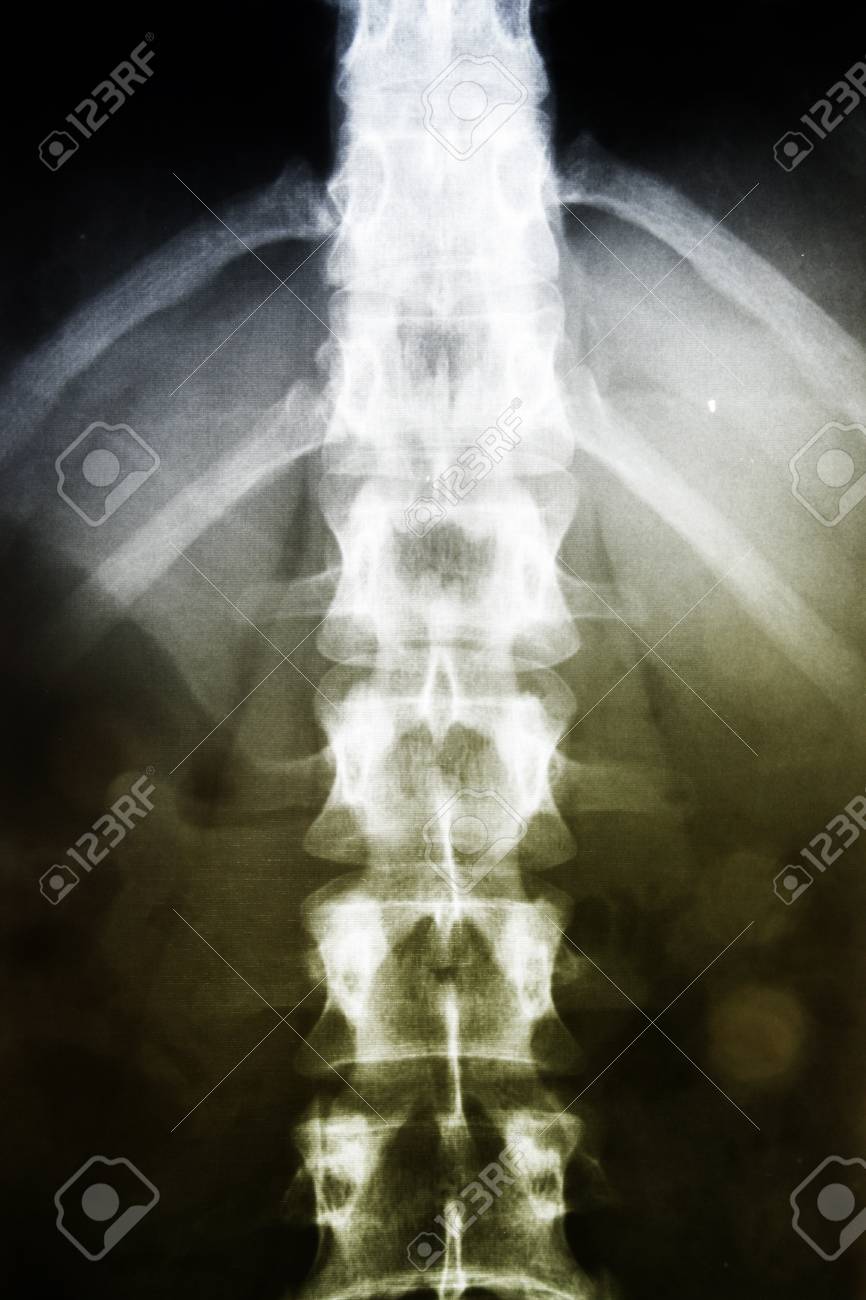

anatomy, back, bones, care, clinic, diagnosis, disc, film, healing, health, healthcare, hospital, human, lamina, ligaments, lumbar, medical, medicine, patient, pelvic, pelvis, radiation, radiography, radiology, ribs, science, seethrough, sickness, skeleton, spinal, spine, tendon, trace, transparent, vertebrae, x ray, xray,